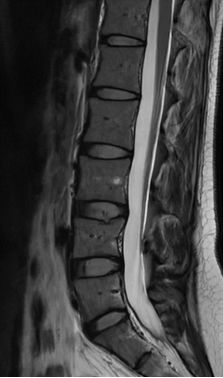

3.MRI(磁共振成像):

优势:无辐射,对软组织(如椎间盘.脊髓.神经根)显示极为清晰,能准确判断椎间盘突出程度.神经根受压情况.脊髓病变等,还可发现隐匿性骨折.软组织肿瘤等。

局限:检查时间较长,体内有金属植入物(如心脏起搏器.金属内固定物)的患者一般不能进行。

适用情况:腰痛伴下肢放射痛.麻木,怀疑腰椎间盘突出.神经根受压.脊髓病变.软组织损伤或肿瘤时。